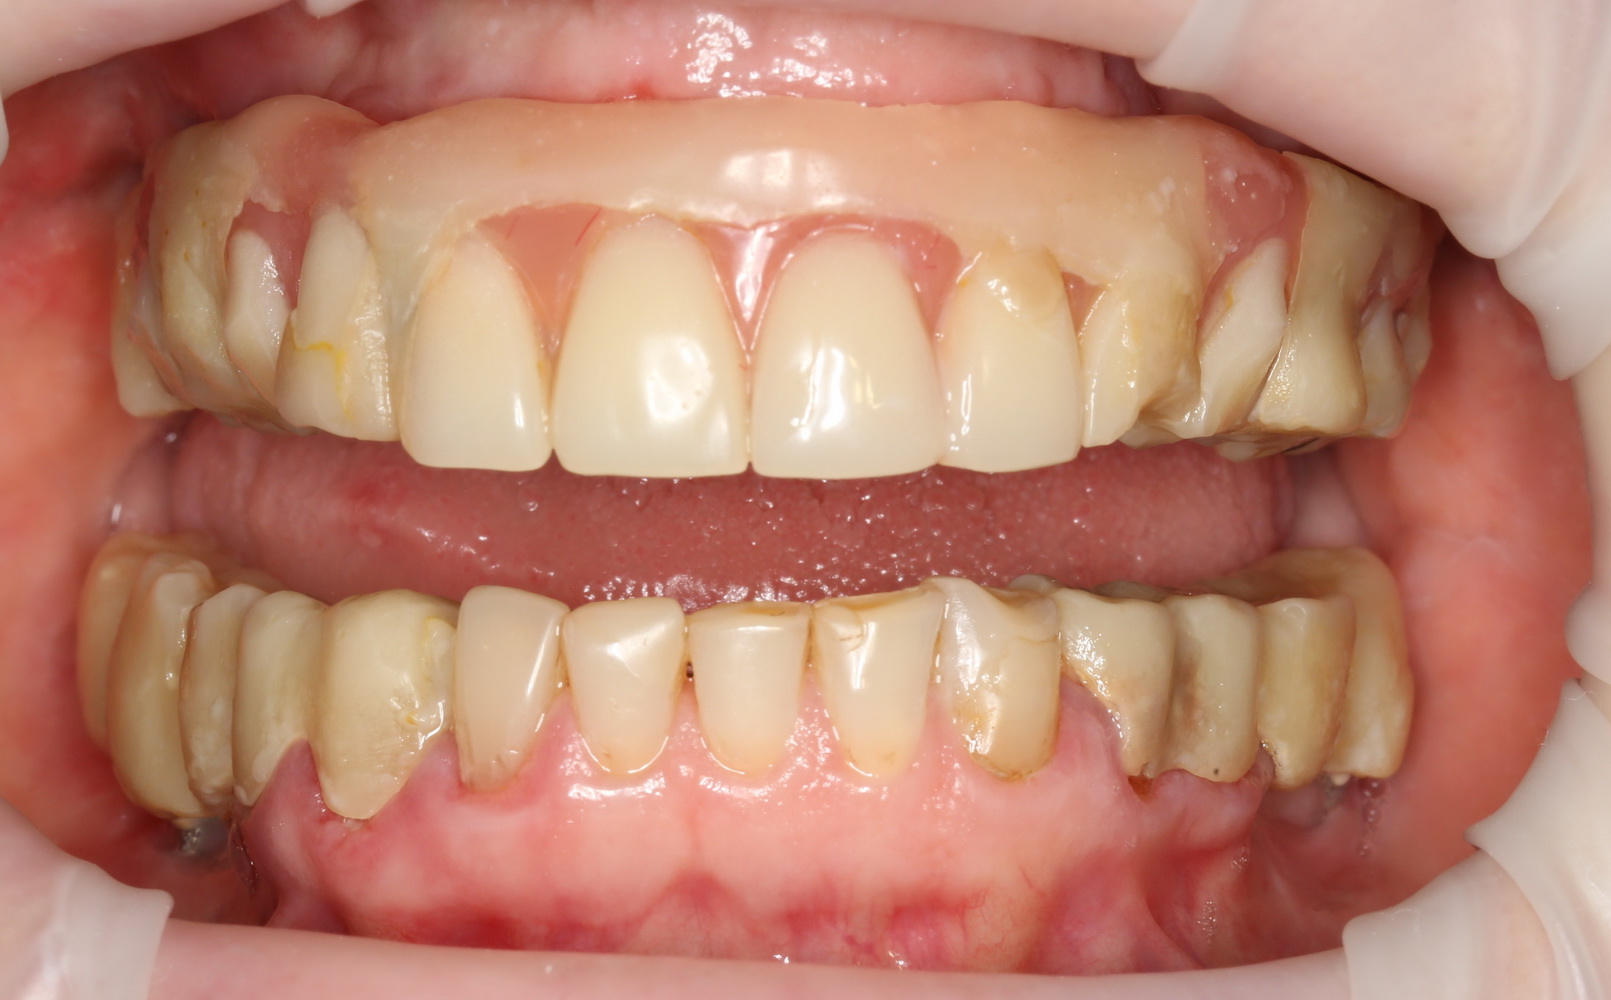

Хотите посмотреть, как на самом деле выглядит протез, изготовленный за 3 дня, и установленный на базальные импланты? Смотрите:

На протезе вы видите следы многочисленных коррекций и ремонтов. Зубы на нижнем и верхнем протезе в боковых участках из-за постоянных подточек, практически потеряли форму, не функциональны. И я объясню вам, почему такое происходит.

Дело в том, что со временем, по мере утраты зубов, у пациента перестраивается весь жевательный аппарат: изменения происходят в челюстных суставах, жевательных мышцах, челюстных костях и т. д. Тотальное протезирование на имплантах — весьма сложная штука, ведь врачу-ортопеду и зубного технику требуется определить такое соотношение челюстей, какое было тогда, когда у пациента еще были все зубы на месте. Это очень сложный, деликатный и важный этап диагностики. Умные доктора это знают, именно поэтому даже при небольшом протезировании используют различные виды функциональной диагностики. Здесь же ничего подобного не было. Работу максимально упростили — ну да, завышают протезы? Подточим! Не смыкаются? Наплавим! А то, что при этом чувствует пациент, что у него происходит с челюстными суставами и жевательными мышцами, как мне кажется, никто не задумывается.